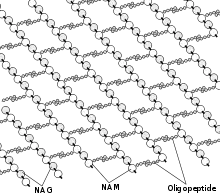

Certaines bactéries sont protégées de l'environnement extérieur par une paroi, qui doit croitre quand la bactérie se divise. Cette paroi contient en particulier une couche de peptidoglycane plus ou moins épaisse, un polymère spécifique comportant des acides aminés et des sucres. Il existe une machinerie de synthèse qui fabrique les composants de cette paroi et qui est composée d'enzymes et de systèmes de transport acheminant les composants à la surface cellulaire.

Il existe un ensemble d'antibiotiques qui bloquent différentes étapes de cette machinerie. Le blocage de la synthèse de la paroi fragilise fortement l'enveloppe externe des bactéries, qui deviennent très sensibles à des stress extérieurs (pression osmotique, température, stress mécanique) provoquant la lyse cellulaire. In vitro, on peut maintenir ces cellules sans paroi avec un stabilisant osmotique, on obtient alors un protoplaste.

Ces antibiotiques agissent sur des cibles extracellulaires. Ils n'ont donc pas besoin de pénétrer dans la cellule, ce qui les rend insensible aux mécanismes de résistance liés à la perméabilité ou à l'efflux (voir plus bas). En revanche, ils ne sont en général actifs que sur les germes en croissance. Les bactéries quiescentes (qui ne se divisent pas) ne sont pas perturbées par l’action de ces molécules, parce que le peptidoglycane n'est produit que lors de la croissance cellulaire, pour s'adapter à l'augmentation du volume précédant la division cellulaire.

Les principaux antibiotiques ayant ce mode d'action correspondant à la famille appelée les Bêta-lactamines (pénicillines et céphalosporines)[7]. Ceux-ci agissent sur les enzymes de la machinerie de synthèse du peptidoglycane que l'on appelle pour cette raison les « protéines fixant la pénicilline » (penicillin binding proteins ou PBP).